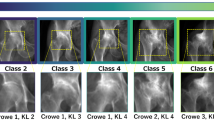

Crowe grade 1 corresponds to subluxation < 50% (Fig. 3A).

Crowe grade 2 subluxation between 50 and < 75% (Fig. 3B).

Crowe grade 3 subluxation between 75 and 100% (Fig. 3C).

Crowe grade 4 total luxation (Fig. 3D).

Dysplastic hip: The femoral head is contained within the original acetabulum despite the degree of subluxation (Fig. 3A & B).

Low dislocation: The femoral head articulates with a false acetabulum that partially covers the true acetabulum to a varying degree (Fig. 3C).

High dislocation: The femoral head is completely out of the true acetabulum and migrated superiorly and posteriorly to varying degrees (Fig. 3D).

We tried to increase the understanding of the model by using saliency maps. Figure 4 shows examples of saliency maps for Normal/Borderline and Crowe 1–4 classifications. The saliency maps showed that the edge of the calcar region of the femur and its relation to the pelvic ring played an important role in the classification. This seems like a method resembling dysplasia classification by relying on Shenton’s line, which is a method that has high accuracy for determining femoral subluxation [32].

Furthermore, the model seemed to use the inferior cortex of the femoral neck arch and its relation to the inner and outer cortices of the pelvic ring (Fig. 5). For the more dysplastic hips that also had more femoral head deformity, the model seemed to recognize a narrower arch between the neck and the deformed head (Fig. 5, Crowe class 3). Although these interpretations are highly subjective and cannot be interpreted as a “logic” being used by the model, it is encouraging to see that the model learned to focus on relevant anatomical areas without any explicit training or “rules” to follow.